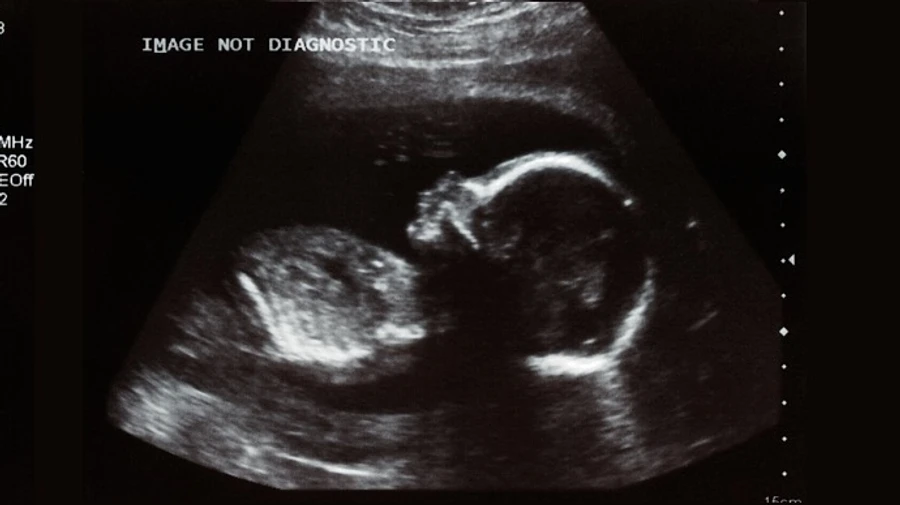

Детали: Изучив историю болезни ребенка и роженицы с COVID-19 исследователи пришли к выводу, что коронавирус может передаваться от беременной женщины к плоду.

В исследовании говорится о ребенке, который родился в марте 2020 года от матери с диагнозом COVID-19 и вскоре дал положительный результат на упомянутую болезнь. Тогда у младенца диагностировали аномалии в мозге, однако ребенок победил болезнь и спустя 3 месяца "имеет медицинские показания близкие к норме". 23-летняя мама ребенка, история болезни которого теперь считается первым случаем внутриутробного заражения коронавирусом, также выздоровела от COVID-19